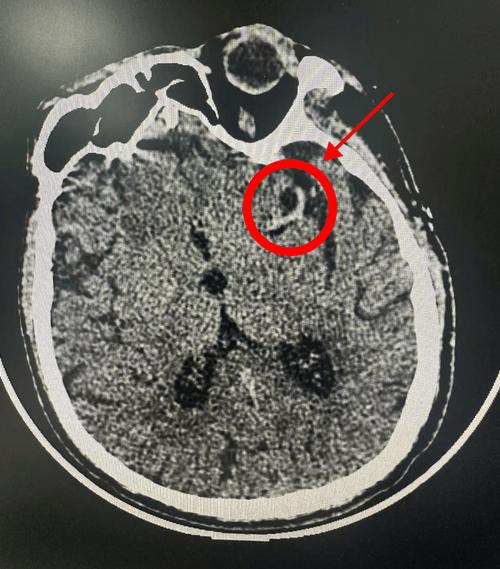

后循环梗死(脑干、小脑梗死): 脑干和小脑位于颅骨后部,骨质结构复杂,与周围脑组织的密度差异较小,CT对这些区域的梗死灶显示不如对大脑半球的病灶敏感,容易漏诊。

(图片来源网络,侵删) -